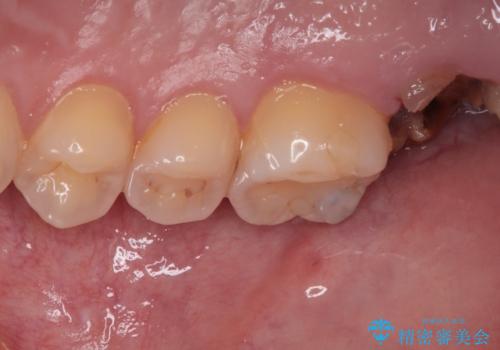

右上のインプラント治療は、1DAYインプラント治療(抜歯即時埋入・即時荷重)の適応となりましたので、通常3回必要な外科処置の回数を1回に集約させることができました。

口腔内の環境が大きく改善し、現在はご自身のプラークコントロールにより良い状態が維持できるようになりました。